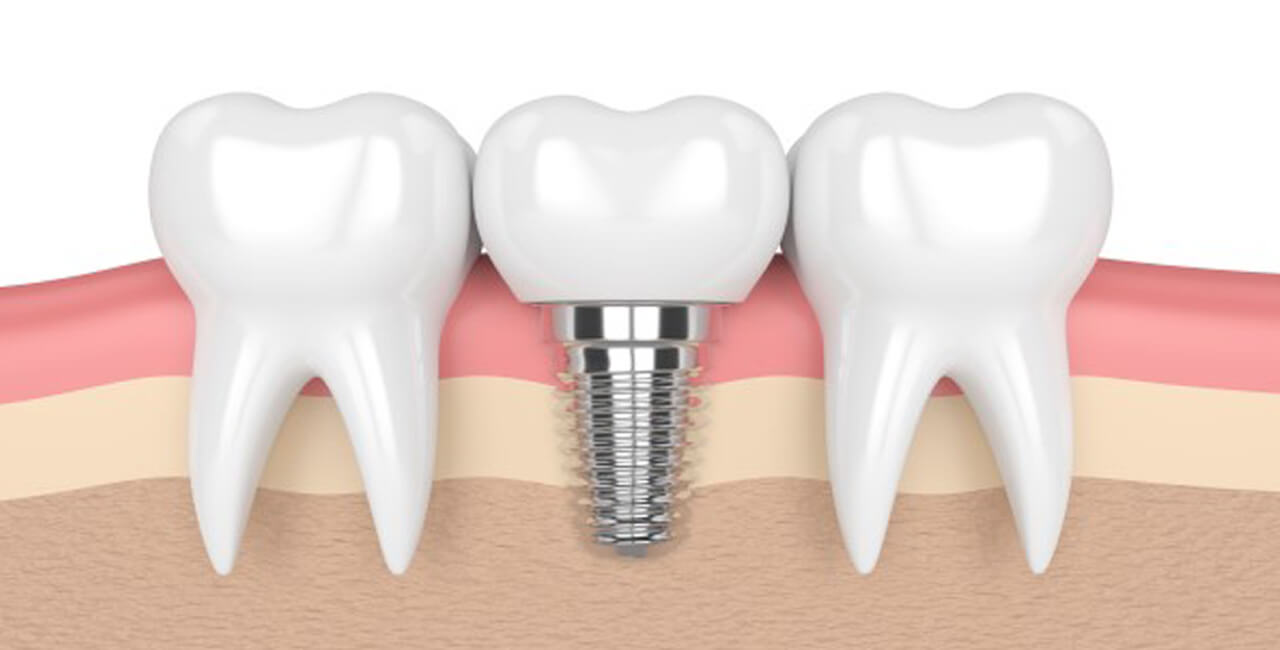

1. **Implant Placement**: The primary focus of implantology is the surgical placement of dental implants. This involves drilling into the patient’s jawbone to insert the implant, which serves as an anchor for the replacement tooth or teeth.

4. **Osseointegration**: A crucial concept in implantology is osseointegration, the process by which the implant fuses with the surrounding bone tissue. This integration ensures the stability and longevity of the implant.

7. **Healing and Integration**: After the implant is placed, there is a healing period during which osseointegration occurs. This can take several months, and temporary prosthetics may be used during this period to maintain aesthetics and functionality.

8. **Prosthesis Attachment**: Once osseointegration is complete, an abutment is attached to the implant, and a prosthetic tooth or teeth (crown, bridge, or denture) is affixed to the abutment. The final restoration is custom-made to match the patient’s natural teeth.